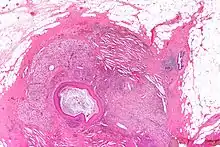

Squamous metaplasia of lactiferous ducts

Squamous metaplasia of lactiferous ducts - abbreviated SMOLD is a change where the normal double layer cuboid epithelium of the lactiferous ducts is replaced by squamous keratinizing cell layers. The resulting epithelium is very similar to normal skin, hence some authors speak of epidermalization. SMOLD is rare in premenopausal women (possibly 0.1-3%) but more frequent (possibly up to 25%) in postmenopausal women where it does not cause any problems at all.

The last section of the lactiferous ducts is always lined with squamous keratinizing epithelium which appears to have important physiological functions. For example, the keratin forms plugs sealing the duct entry and has bacteriostatic properties. In SMOLD the keratinizing lining which is supposed to form only the ends of the lactiferous ducts extends deep into the ducts.

The keratin plugs (debris) produced by SMOLD have been proposed as the cause for recurrent subareolar abscesses by causing secretory stasis. The epidermalized lining has also different permeability than the normal lining, hindering resorption of glandular secretions. The resorption is necessary to dispose of stalled secretions inside the duct - and at least equally important it affects osmotic balance which in turn is an important mechanism in the control of lactogenesis (this is relevant both in puerperal and nonpuerperal mastitis).